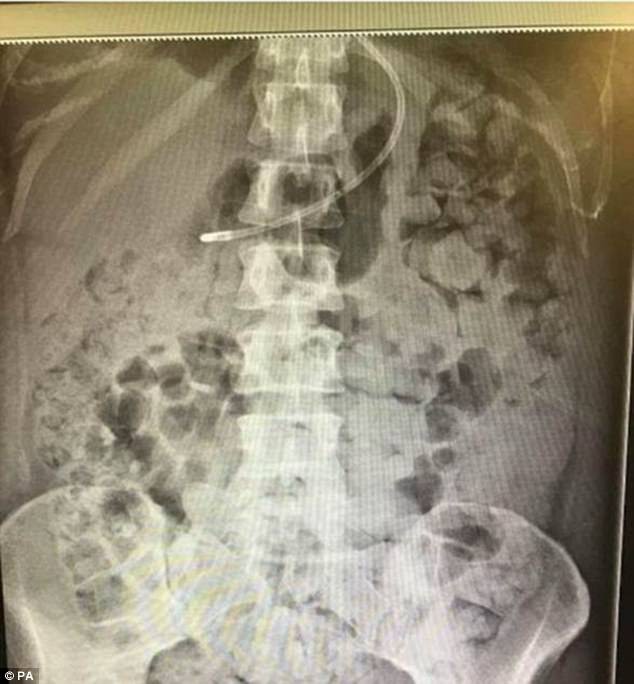

Tấm hình chụp X quang cho thấy, toàn bộ nội tạng của Kelly đã bị “nhấn chìm” trong chất thải. Phổi cô bị chèn ép đến mức cô không thể hô hấp được bình thường. Kinh khủng hơn nữa, Kelly còn thường xuyên nôn ói sau khi ăn thậm chí là nôn ra cả chất thải.